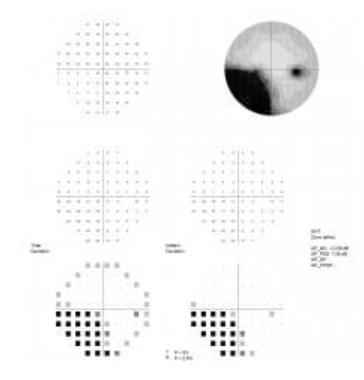

Perymetr komputerowy AP-300

AP-300 to nowoczesny perymetr komputerowy spełniający najwyższe standardy w diagnostyce pola widzenia. Zapewnia zaawansowaną diagnostykę z użyciem perymetrii kinetycznej i statycznej, w tym perymetrii Blue on Yellow. Urządzenie oferuje szeroki wybór strategii, pól i parametrów badania. Wbudowana kamera zapewnia automatyczną kontrolę fiksacji pacjenta. Wbudowane funkcje analizy danych obejmują analizę regresji pola widzenia na podstawie historii badań oraz zestandaryzowane sposoby prezentowania i drukowania wyników badań. Intuicyjne oprogramowanie perymetru umożliwia łatwą obsługę urządzenia i jest przystosowane do obsługi za pomocą ekranów dotykowych. Perymetr AP-300 ma wbudowany komputer klasy PC.

AP-300 jest urządzeniem łączącym w sobie cechy perymetrów statycznych i kinetycznych oferującym bogaty zestaw technik diagnostycznych. Zaawansowane oprogramowanie użytkowe urządzenia oferuje bogate funkcje analizy wyników badania ułatwiając diagnozę. Dostępne w standardzie metody prezentacji wyników pozwalają na wydruki dla pojedynczego badania jak i przedstawienia zmian zachodzących w polu widzenia pacjenta w czasie.

Prezentacje i wydruki wyników

Wynikowa czułość pola widzenia może być przedstawiona w formie prezentacji numerycznej, skali szarości, skali kolorowej, skali kropkowej bądź trójwymiarowej mapy. Prezentacje mogą przedstawiać wartości bezwzględne w decybelach, wzgórze widzenia, odchyłki od normy wiekowej oraz krzywą defektu (Bebiego).

Oprogramowanie umożliwia drukowanie wyników w formie standardowej mapy 7 in 1 (7 prezentacji wyniku na jednej stronie) oraz w wielu innych formatach podlegających edycji.

Różnorodna prezentacja wyników badania

Wyniki badania mogą być wyświetlane w różnorodny sposób:

- w skali numerycznej, kolorowej, szarości bądź kropkowej,

- jako wartości bezwzględne w dB, wzgórze widzenia, odchyłka od normy wiekowej, wykresy prawdopodobieństwa występowania defektu,

- jako krzywa defektu (Bebiego),

- w postaci mapy znormalizowanej.